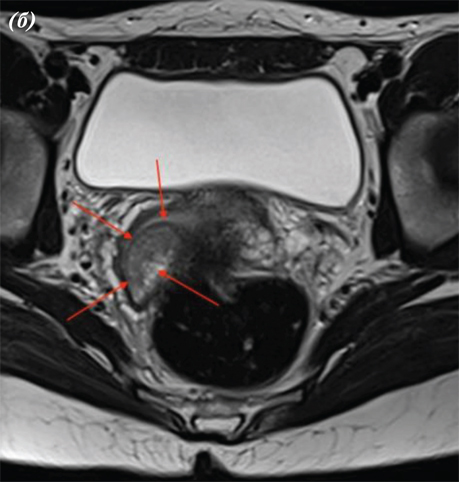

Взято біопсію шийки матки. Патогістологічний висновок: у матеріалі біопсії з урахуванням результатів морфологічного та ІГХ дослідження серед крові визначаються фрагменти тканини шийки матки, інфільтровані елементами інвазивної плоскоклітинної HPV-асоційованої карциноми G1 (low grade) (рис. 1).

Рис. 1. Рак шийки матки — інвазивна плоскоклітинна HPV-асоційована карцинома G1 (low grade)

Фрагмент тканини шийки матки переважно заміщений розростаннями злоякісних епітеліальних клітин, диспластичний багатошаровий плоский епітелій через базальну мембрану поширюється в прилеглу волокнисту сполучну тканину без прикріплення до поверхні, клітини пухлини з вогнищевим плеоморфізмом, наявні фігури мітозів, некрози відсутні, клітини пухлини з крупними гіперхромними базофільними ядрами та переважно скудною еозинофільною цитоплазмою, з наявністю внутрішньоклітинних містків, пухлина солідно-гніздового типу росту, без ознак ороговіння, без формування кератинових мас (рис. 2).

При виконанні магнітно-резонансної томографії (МРТ) органів черевної порожнини та малого таза від 15.03.2023 р. виявлено, що заочеревинні лімфатичні вузли не збільшені. Тіло матки розміром 45×46×47 мм. Зональна структура збережена, відповідно віку. Зовнішній контур тіла матки чіткий та рівний. Шийка матки — структурна, розміром 25×20×30 мм. Цервікальний канал рівний та чіткий. У проєкції входу в шийку матки по правій стінці на 5 год умовного циферблату виявлено екзофітний інфільтрат розміром 12×12 мм. Параметральна клітковина не змінена.

Рис. 4. МРТ органів черевної порожнини пацієнтки. МРТ-ознаки РШМ, без поширення на суміжні органи: a — сагітальна проєкція; b — фронтальна проєкція